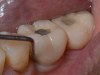

Similar to natural teeth, measurements of PPD and BoP before and after treatment are clinical parameters often used to determine the health of dental implants (Figure 4 and Figure 5). However, due to the difference between periodontal and peri-implant anatomy, concerns have been raised about the use of probes in peri-implant tissues around dental implants. These include the risk of peri-implant tissue damage,17,18 risk of damage to the implant surface by the metallic probe,19-21 risk of bacteria inoculation,22-27 and risk of galvanic corrosion resulting from contact between two dissimilar metals.21,28-30 These risks are discussed in the following sections.

Fig 4. Increased probing depth around an implant with BoP indicates presence of peri-implant disease and the need for taking a radiograph.

Fig 5. Bone loss shown on radiograph confirms the presence of peri-implantitis and peri-mucositis.